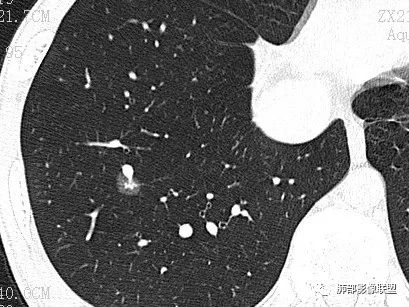

MGGO,边界清楚,胸膜凹陷,考虑LPA?

F 053Y 体检发现 医学百科网 | YxBaike.Com

混合GGO,收缩力弱,部分边缘似清非清,圆洞样胸膜凹陷

近胸膜处,边缘似清非清,血管进入,胸膜凹陷,结合CT值,考虑IAC 医学百科网 | YxBaike.Com

混合磨玻璃,收缩力弱,部分边缘似清非清,圆洞样胸膜凹陷,血管进入增粗,LPA,粘液腺癌?

王兆宇:CT值中央区偏高 医学百科网 | YxBaike.Com

王兆宇:边界很清楚啊

@江登科 内部的高密度区>5mm

是大于5mm IAC(浸润性腺癌) 胸膜还是有牵拉

这例圆洞样的胸膜,造成一定难度

圆洞的底不太光滑

牵拉洞壁不够光滑,洞底感觉坑坑洼洼的 医学百科网 | YxBaike.Com

病理结果

浸润性腺癌 医学百科网 | YxBaike.Com

病理结果没有记录附壁生长的成分。我认为附壁生长为主型LPA。通常收缩力明显的,是裂隙状胸膜凹陷 但在肺尖部,可能胸膜有一定的壳样增厚,所以可以圆洞样 医学百科网 | YxBaike.Com

一句话小结:

胸膜下孤立较大混合密度结节影,中央实行密度,周围磨玻璃边界清楚提示存在小叶间隔阻挡。局部明显胸膜凹陷,提示病灶较强收缩能力,这也很少见于粘液腺癌。 医学百科网 | YxBaike.Com

综上更符合浸润性腺癌。